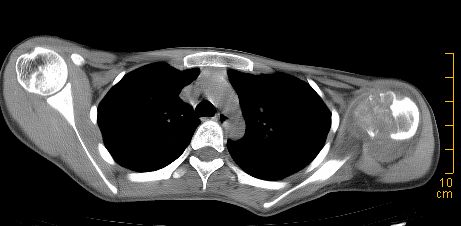

标题: CT22395:左侧肱骨头占位性病灶。 [打印本页]

标题: CT22395:左侧肱骨头占位性病灶。

这是一个17岁的花季少女,在上学期间,自觉左侧肩部不适,家人误以为是外伤引起,没有重视,近日疼痛加剧,来院就诊,ct检查发现如下.

诊断依据:1、骨质破坏,软组织肿胀。2、从纵隔窗上看,这么年轻就有纵隔淋巴结钙化,提示有可能有肺结核病史,这是诊断左肩关节结核的又一重大证据,建议结合病史并提供肺窗。

鉴别诊断:成软骨细胞瘤(位于骨骺内,囊状破坏,一般不会有软组织肿胀)

骨质膨胀性破坏,软组织肿胀,有新骨形成。考虑骨肉瘤